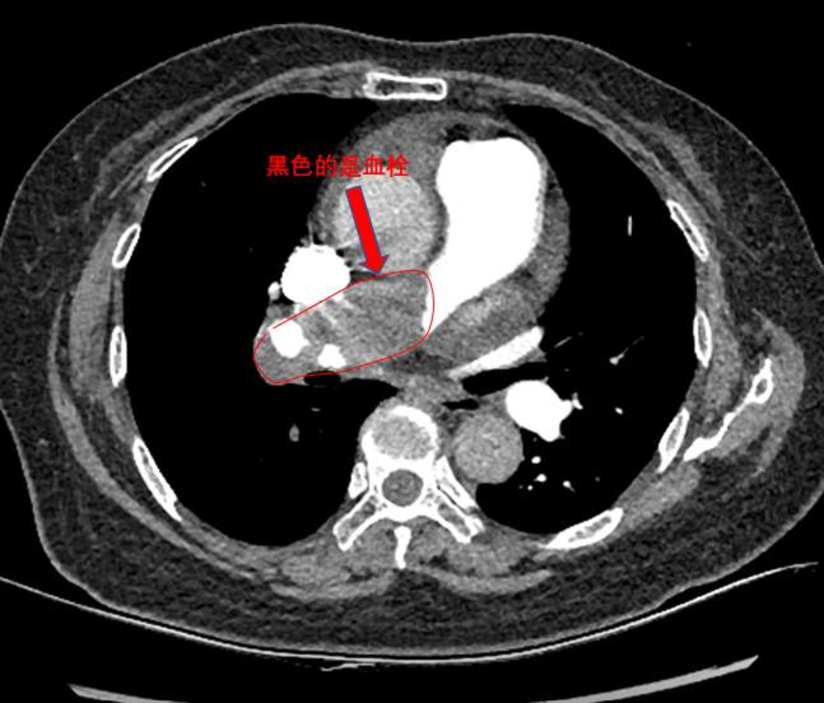

当天120急救送到了我们科室。只见王阿姨表情痛苦,口唇、指端明显紫绀,气喘得不能讲话,端坐在床上,无法躺平,双腿肿的很厉害。心率116次/分,血压90/50mmHg,血氧饱和度80-85%。急查血,氧分压49.4mmHg,心衰指标(NT-proBNP):15378pg/ml,D-二聚体:4219ng/ml,心电图示窦性心动过速。胸片提示肺动脉段突出,心影明显增大(图1)。

下肢静脉彩超提示双侧小腿多支静脉血管血栓形成。心超彩超示重度肺动脉高压(肺动脉收缩压101mmHg),右心明显增大,TAPSE:1.68cm,少量心包积液(图2)。肺动脉CT(CTPA)示主肺动脉及右肺动脉干明显增宽,右肺动脉干见巨大充盈缺损,叶、段肺动脉均未显影;左侧肺动脉多发分支充盈缺损(图3)。肺动脉造影提示右肺动脉叶段分支均未显影(图4)。

综合以上情况,考虑肺栓塞(考虑慢性肺血栓,本次急性发作)、慢性血栓栓塞性肺动脉高压、心力衰竭、呼吸衰竭诊断,病情危重,随时可能猝死。考虑血栓负荷大,给与肺动脉吸栓术,术后右肺动脉叶段多支显影,见下图。